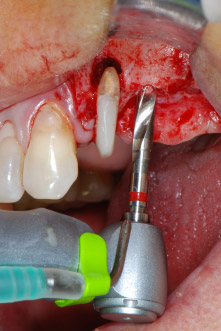

След един месец, в деня на операцията, болката и възпалението в зъб 24 е минимално, но подвижността в Miller class 2 е на лице. След отваряне на ламбата и почистването на периапикалната и перирадикуларната тъкани, обхватът на костния дефект стана очевиден (Фиг. 2 и 3).

В букалния корен, цялата вестибуларна и дистална кост липсва. Захващането е значително ограничено до палатиналния корен, подчертавайки предварително лошата прогноза. Зъб 27 също откри намалено хоризонтално захващане и минимално апикално разреждане (Фиг. 1) без клинични симптоми.

тотална загуба на кост и захват

Фиг. 2 и 3: След повдигане на ламбото, един месец след ендодонтския преглед и прилагане на цялостна периодонтална терапия в цялата уста, букалният корен на зъб 24 разкри тотална загуба на кост и захват.

Въпреки това, ние се придържахме към първоначалния си план да запазим и двата зъба като абатмънти за временен мост по време на 6-месечната остеоинтеграция на имплантите. При повторна интервенция, ситуацията трябва да се преразгледа. Първо, в опит да се овладее ендо-перио проблема, останалата повърхност на зъба е внимателно обработена с пиезохирургично оборудване (Piezomed, W&H, използван с накрайник S1 под формата на шпатула, първоначално проектиран за ерозия на латералната синусна стена) (Фиг. 4).